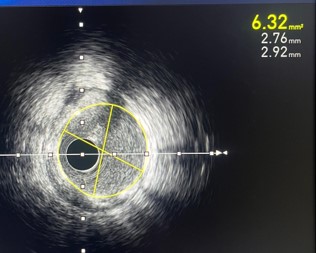

Post rotational atherectomyangiogram and IVUS run taken

In view of 300-360 degrees ofcalcium arc and not good MLAs in mid and proximal RCA post ROTA we decided todo Intravascular lithotripsyIntravascular lithotripsy with 3.0x12mm balloon done in mid and proximal RCA

Post rotational atherectomyangiogram and IVUS run taken

In view of 300-360 degrees ofcalcium arc and not good MLAs in mid and proximal RCA post ROTA we decided todo Intravascular lithotripsyIntravascular lithotripsy with 3.0x12mm balloon done in mid and proximal RCA